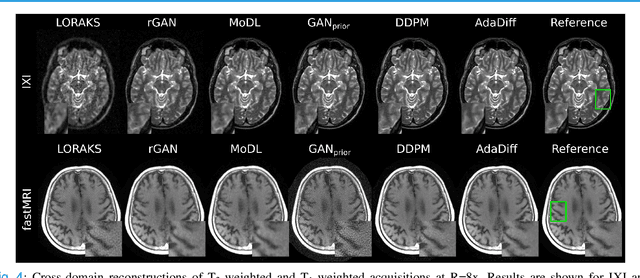

Abstract:Deep MRI reconstruction is commonly performed with conditional models that map undersampled data as input onto fully-sampled data as output. Conditional models perform de-aliasing under knowledge of the accelerated imaging operator, so they poorly generalize under domain shifts in the operator. Unconditional models are a powerful alternative that instead learn generative image priors to improve reliability against domain shifts. Recent diffusion models are particularly promising given their high representational diversity and sample quality. Nevertheless, projections through a static image prior can lead to suboptimal performance. Here we propose a novel MRI reconstruction, AdaDiff, based on an adaptive diffusion prior. To enable efficient image sampling, an adversarial mapper is introduced that enables use of large diffusion steps. A two-phase reconstruction is performed with the trained prior: a rapid-diffusion phase that produces an initial reconstruction, and an adaptation phase where the diffusion prior is updated to minimize reconstruction loss on acquired k-space data. Demonstrations on multi-contrast brain MRI clearly indicate that AdaDiff achieves superior performance to competing models in cross-domain tasks, and superior or on par performance in within-domain tasks.